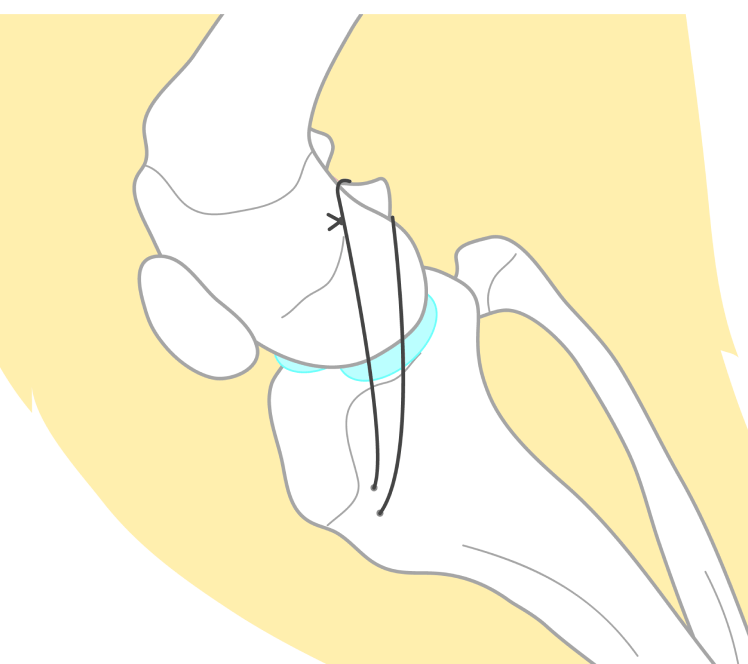

関節外制動法(Floの変法)

手術には主に2種類の方法があります。1つは、膝関節の外部に強力な人工素材や縫合糸を通して、切れてしまった前十字靭帯の役割を補うことで、脛骨が前方に滑らないようにします。これにより、膝を安定化させます。

メリット

骨に小さな穴を開けて紐を通して縛るという手技のため後述するTPLO法と比較して、手術が短時間で済みます。

デメリット

体重の重い大型犬では、かけた紐が緩みやすく関節外法による安定が不十分になることがあります。また、関節の可動域が制限されやすく、術後に症状が改善するまでの時間がTPLO法よりも長くなります。

これらの手術法は、個々の症例の状態に応じて実施されます。術後は適切なリハビリテーションが重要で、専門的なケアにより良好な回復が期待できます。